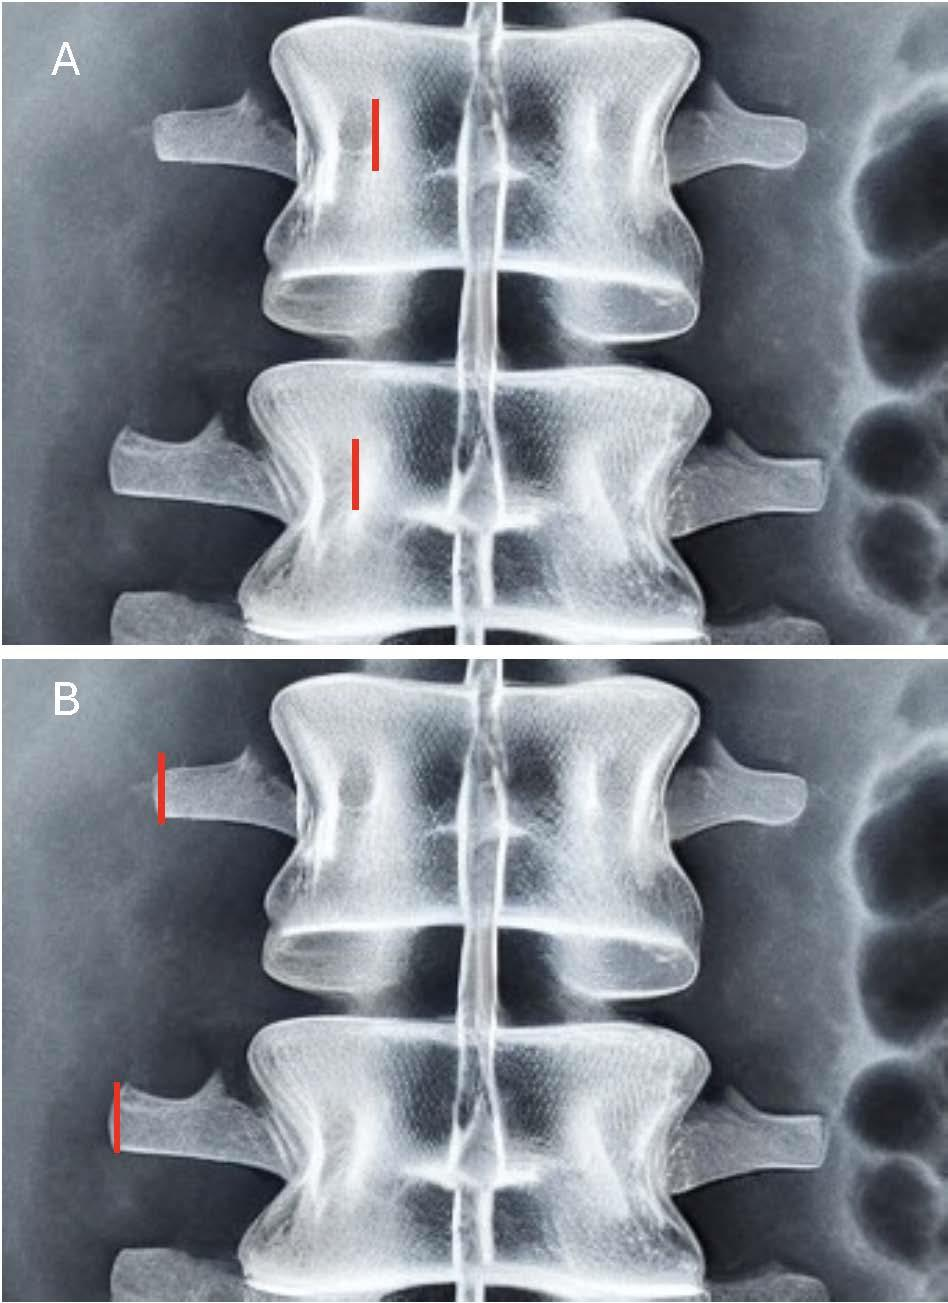

在UBE中,观察通道与工作通道相分开,这种分离内镜和手术工具独立移动,这些空间的精确位置对于可视化至关重要。在腰椎手术中,切开通常沿着椎弓根建立,以提供直接进入椎管的通道,从而根据需要进行减压或椎间盘切除。观察口通常位于更靠头端的位置,旨在容纳内镜。工作通道位于更靠尾端的位置,用于放入手术工具,如咬骨钳、骨凿和磨钻。对于后外侧入路,工作通道传统上放置在尾端椎弓根的内侧缘,观察通道位于工作工作通道头端约3cm处,或与椎弓根内侧边缘对齐。对于椎间孔入路,在两个椎弓根外侧边缘外侧约3cm处做两个切口,与横突横突对齐。然后通过在椎间孔识别头端、下关节突和上关节突来建立工作通道。传统上,通道的位置是通过透视确定的。然而,在最初的学习阶段,3D导航对于准确识别切口位置和帮助外科医生在手术过程中失去空间意识特别有用。尽管这些是传统的切口位置,但由于操作习惯、外科医生的优势手和其他解剖学因素也可以有一些变化。